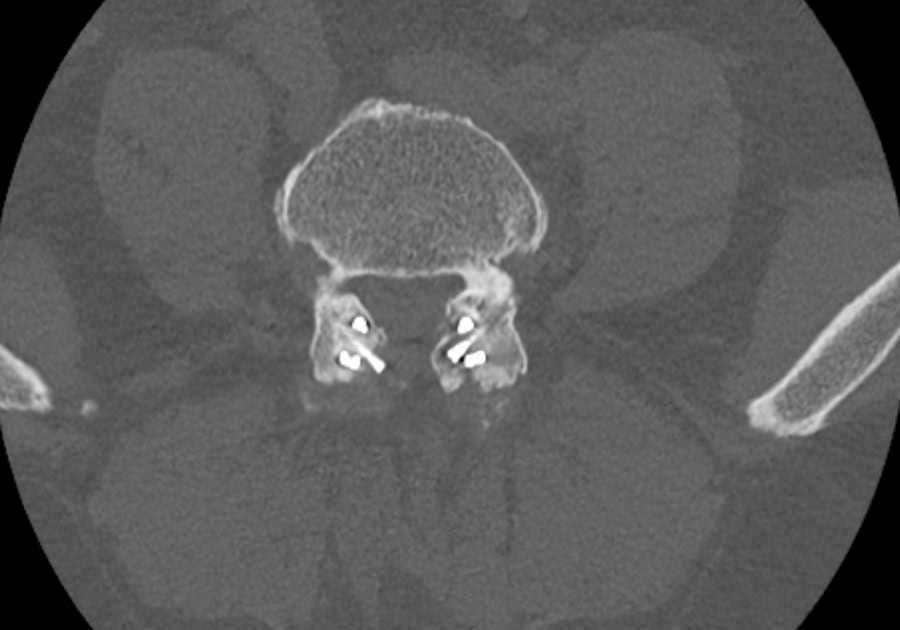

Preop.

2-year Postop.